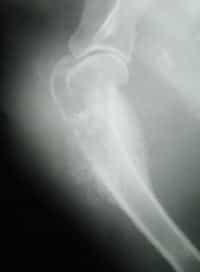

Tumore alle ossa

Causato da un improvviso cambiamento anche di una sola cellula del nostro corpo, il cancro si presenta in numerose forme e può colpire molti organi; quello che stupisce è che il tempo di incubazione di questa patologia può variare a seconda dei diversi casi. È infatti possibile che un cancro si sviluppi all’interno del corpo… Continua a leggere Tumore alle ossa